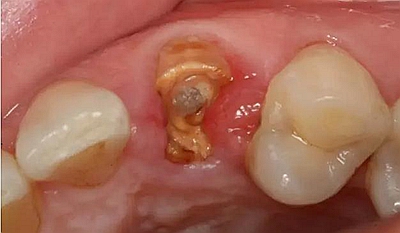

患者男性,35歲,B6銀汞充填后食物嵌塞,要求重新充填,口內(nèi)檢查見B6近中鄰頜面銀汞充填物,局部缺損,有繼發(fā)齲,去除原充填物及繼發(fā)齲,發(fā)現(xiàn)齲壞位于牙齦下方,給予冠延長(zhǎng)手術(shù),同期嵌體預(yù)備,后一次性取模。(同樣設(shè)計(jì)為齦上邊緣)

硅橡膠取模后,灌注模型,科爾琥珀樹脂制作嵌體。

一周后拆線,口內(nèi)試戴合適,粘結(jié)嵌體。